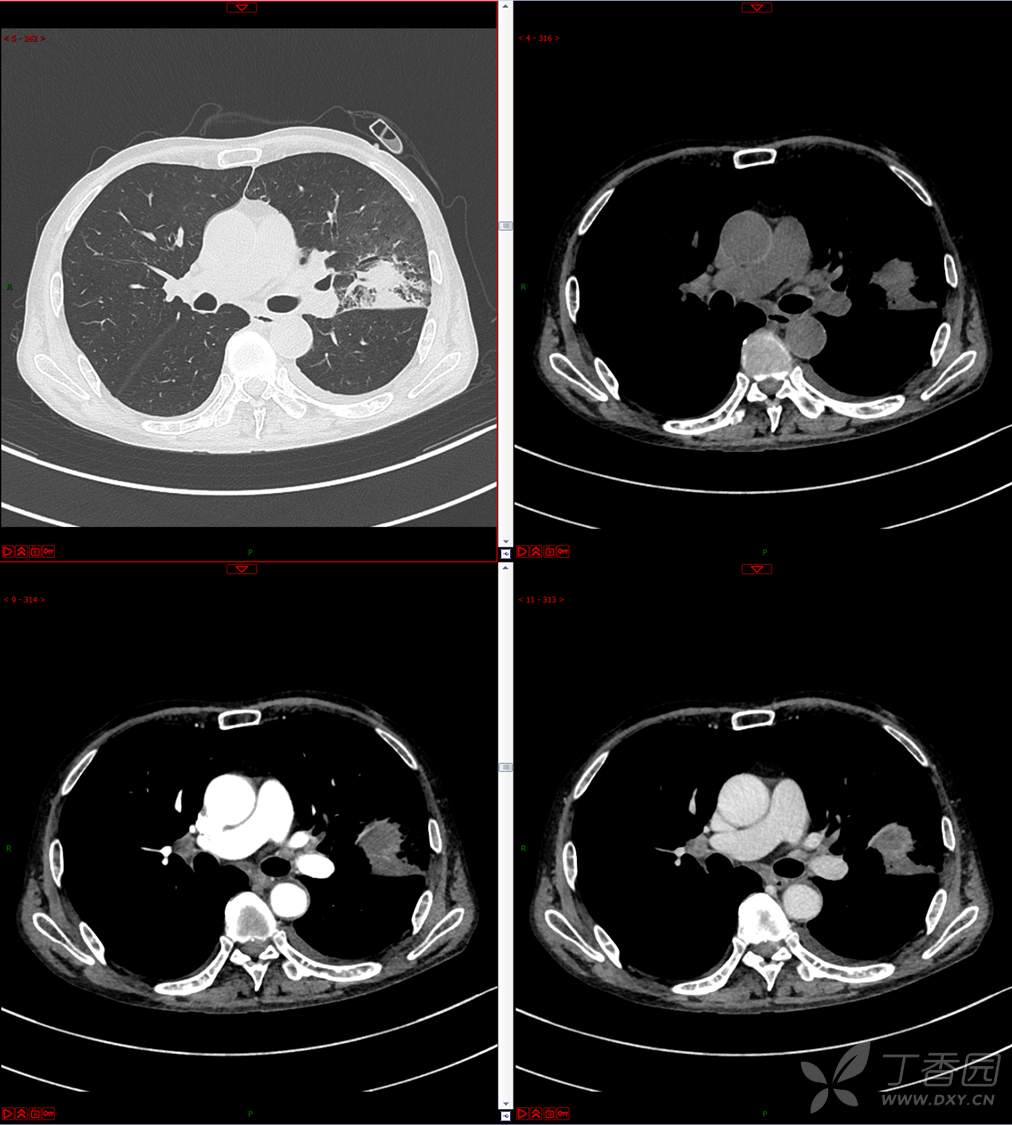

现病史:患者自诉5月前无明显原因及诱因出现纳差、乏力,伴进食后腹胀,无腹痛、腹泻、发热、盗汗、恶心、胸闷,未行特殊处理。1月前无明显原因诱因出现咳嗽,呈阵发性,咳白痰,痰中带鲜红色血丝,10余口/日,无血块,仍伴纳差、乏力、进食后腹胀,无恶心、呕吐、呕血,无头晕、心慌、喘憋、胸闷。在家未行特殊治疗,来我院就诊,2022.8.18行胸部(肺)CT平扫:左上肺占位并左侧肋骨骨质破坏,考虑间叶源性恶性肿瘤。门诊以“肺肿物”收入我科。患者自发病以来,神志清,精神可,饮食差,睡眠可,二便正常,近3月减轻5Kg。